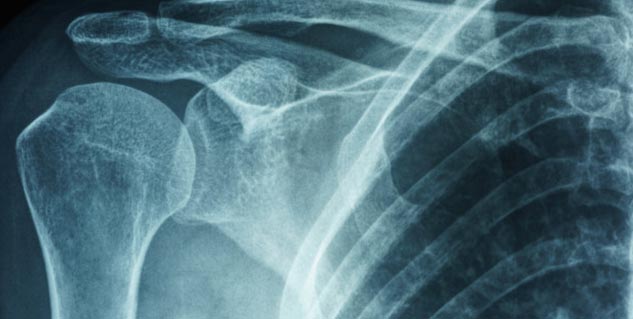

डायबिटीज (Diabetes) से ग्रस्त कुछ लोग फ्रोजन शोल्डर (Frozen Shoulder) की समस्या का भी सामना करते हैं, जिसके कारण उन्हें काफी समस्याओं का सामना करना पड़ता है। फ्रोजन शोल्डर में शोल्डर के जोड़ सूजने लगते हैं और स्थिति धीरे-धीरे बढ़ती रहती है। जब कंधों की बॉल और सॉकेट जॉइंट में मोबिलिटी कम होने लगती है तो कंधे के मूवमेंट में दिक्कत महसूस करते हैं तो इसी स्थिति को फ्रोजन शोल्डर कहा जाता है। आज का हमारा लेख इसी विषय पर है। आज हम आपको अपने इस लेख के माध्यम से बताएंगे कि डायबिटीज में फ्रोजन शोल्डर (Frozen Shoulder in diabetes) क्यों होता है? साथ ही इसके कारण, लक्षण और बचाव भी जानेंगे। पढ़ते हैं आगे...

डायबिटीज में फ्रोजन शोल्डर होने का कारण (Causes of Flozer Shoulder in Diabetes)

- हमारे शोल्डर में कॉलेजन मौजूद होता है जो हड्डियों को जोड़ों से जोड़ता है।

- ऐसे में डायबिटीज का प्रभाव इस कॉलेजन पर पड़ सकता है, जिसके कारण ये शुगर मॉलिक्यूल कोलेजन को चिपचिपा बना सकते हैं।

- ऐसी स्थिति में लिगामेंट्स और टेंडन कमजोर होने लगते हैं, जिसके कारण कंधा सख्त हो जाता है और मूवमेंट नहीं कर पाता। इस स्थिति को फ्रोजन शोल्डर कहते हैं।